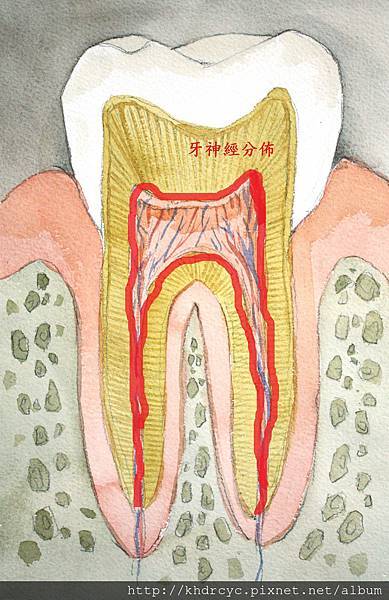

這到底是怎麼回事呢 我們來看這張圖

這是正常牙齒的結構 我們要認識牙神經的位置

這樣我們就可以看懂下面這張圖: